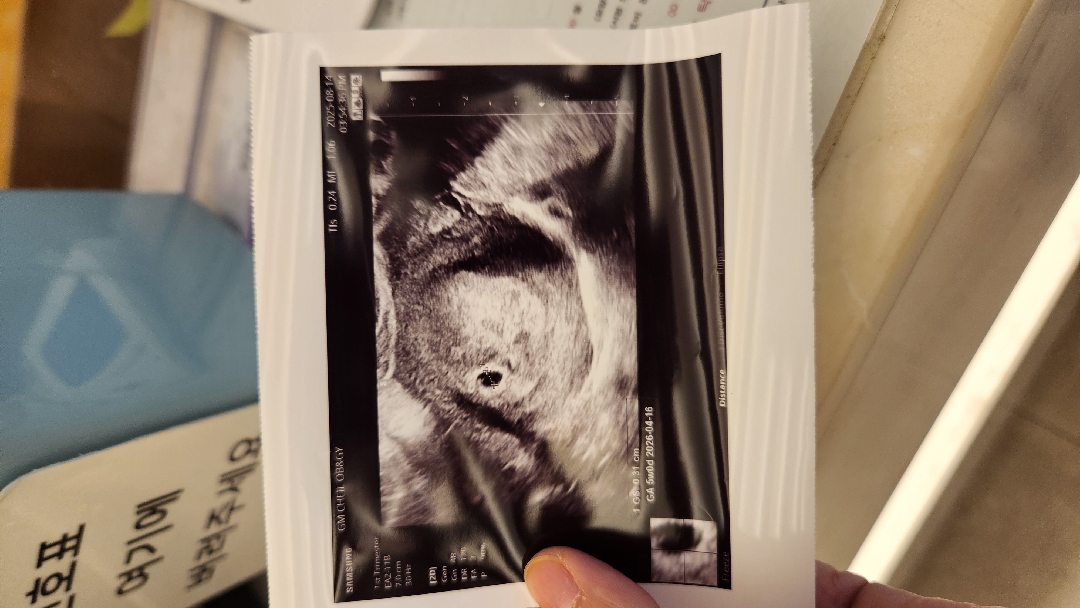

5주차 아기집 보고 왔어요!!

떨리는 맘으로 아기집 보고 왔는데 예상대로 5주차고,아직 난황은 안보인다네요..ㅠ아쉽..2주 뒤에 오라고 하셨는데 다음주에 서브병원에서 촘파 보고 가도 문제 없겠죠??